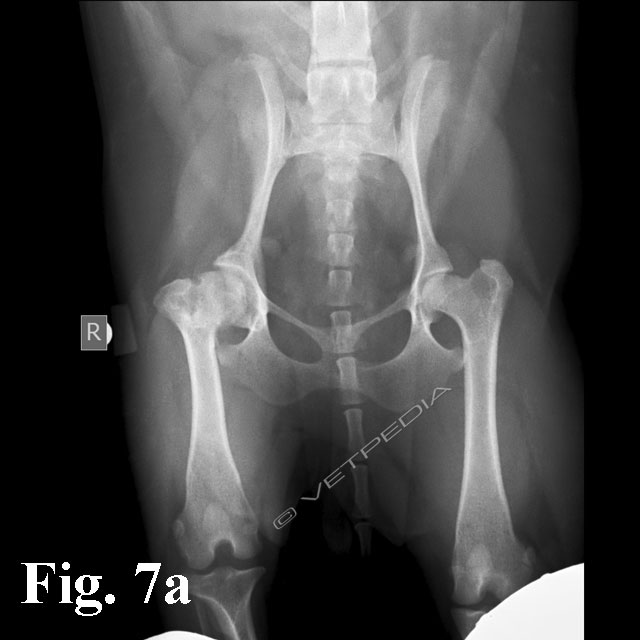

{{/_source.additionalInfo}}La necrosi asettica della testa del femore è anche denominata malattia di Legg Calvè Perthes e necrosi avascolare della testa del femore. Si tratta di un'affezione ortopedica coinvolgente l’articolazione coxofemorale di cani di razza toy o di piccola taglia durante il periodo dell’accrescimento, ad interessamento più frequentemente monola